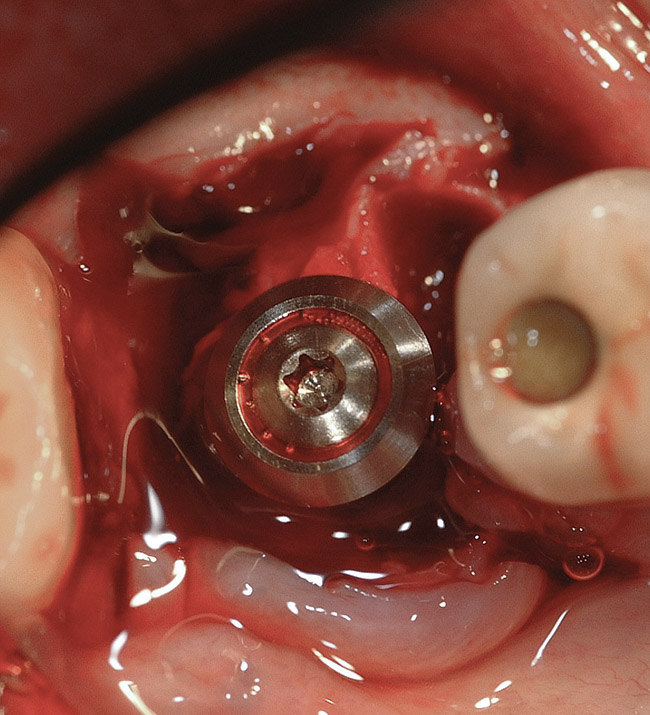

If the most crestal aspect of the interradicular bone is at least 3-mm-wide mesio-distally: A 2.2-mm-wide guide bur is drilled to the appropriate length, a guide pin is inserted, and a radiograph is taken (Figure 7). If necessary, the initial osteotomy is extended apically. A tapered osteotome is inserted into the osteotomy and moved mesio-distally and bucco-lingually to expand the osteotomy site. A 2.8-mm bur is used to prepare the osteotomy to depth, and a 2.8-mm-wide tapered osteotome is inserted in the osteotomy and once again utilized in mesio-distal and bucco-lingual directions to expand the osteotomy site. If the mesial and distal aspects of the interradicular bone are still intact at this point, a 3.5-mm bur is utilized to prepare the osteotomy to depth. A 3.5-mm-wide osteotome is inserted into the osteotomy and utilized in the manner already described. A decision is made as to whether to place a tapered implant with a 4.1-mm-wide base and a 6.5-mm-wide neck, or to use a 4.8-mm-wide bur and prepare the osteotomy to depth, in anticipation of placement of an implant with a 4.8-mm-wide parallel wall body and a 6.5-mm-wide platform. The chosen implant is inserted into the osteotomy (Figure 8), appropriate regenerative materials are placed, and the flaps are sutured. Following maturation of the regenerating hard tissues, the implant is ready for restoration (Figure 9). A radiograph taken 54 months after implant restoration demonstrates stability of the peri-implant crestal bone (Figure 10).